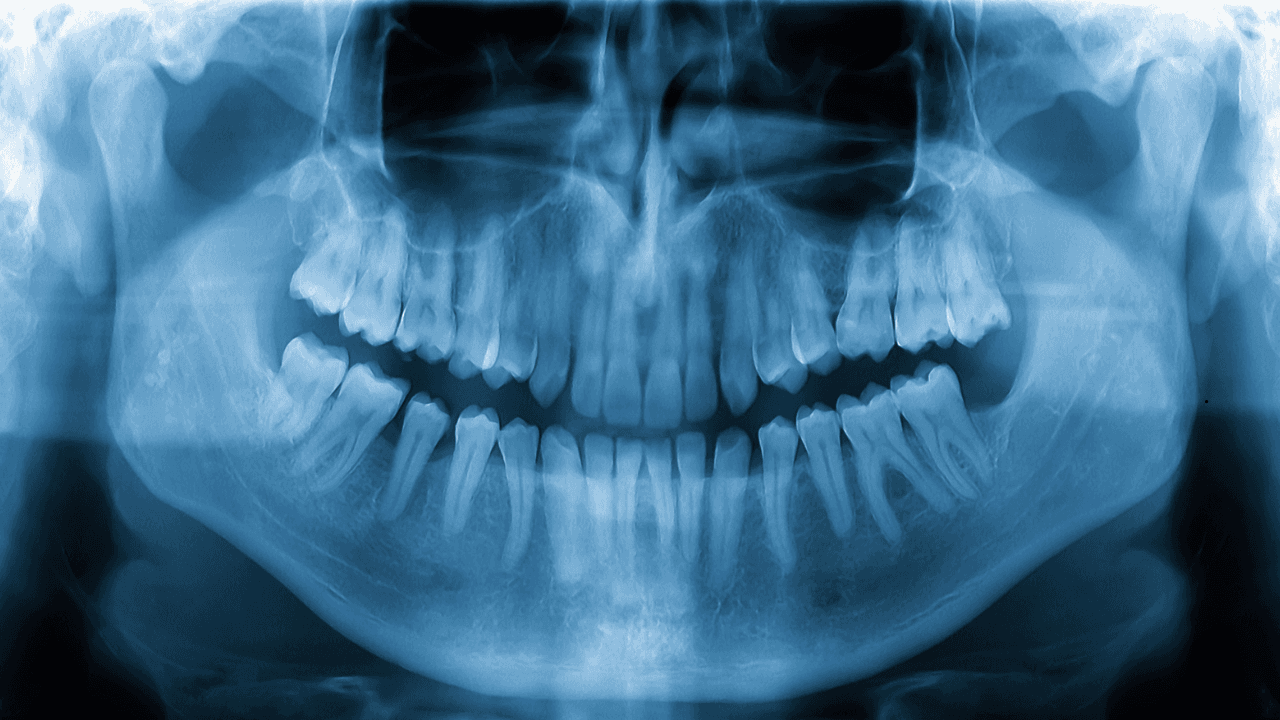

- Panoramic X-Rays: These provide a broad view of the jaws, teeth, sinuses, and nasal areas. They are often used in planning treatments for dental implants or checking the alignment of your jaw.

Dental X-rays provide clear images of your teeth, bones, and the tissues surrounding them. They uncover hidden dental issues before they become serious. By using X-rays, dentists can detect gum diseases, bone loss, and infections at their earliest stages. Without this technology, many dental conditions would remain unnoticed until they cause severe pain or damage.